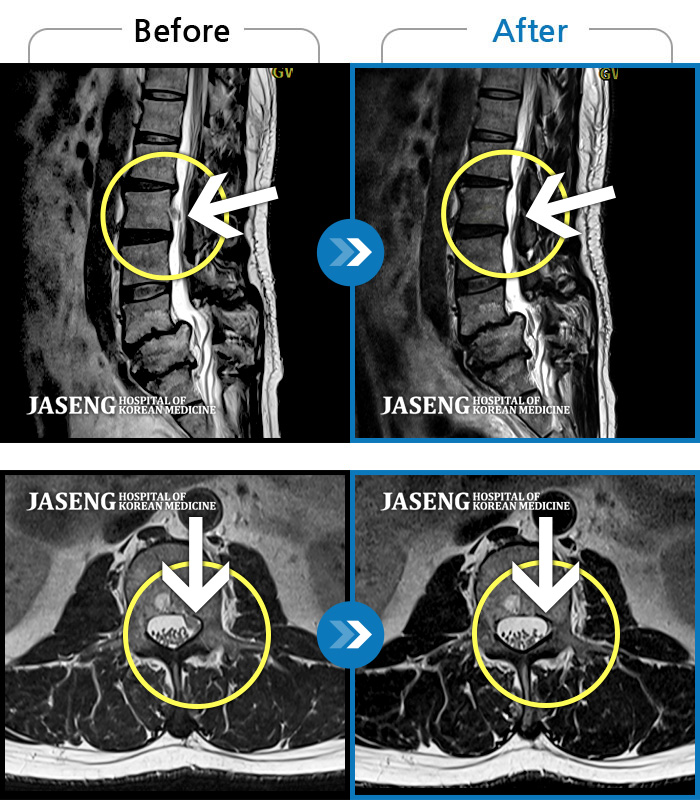

Before

After

환자에게 사전 동의를 받아 동일 조건에서 촬영되었습니다.

개인에 따라 치료 후 부작용이 발생할 수 있으니 의료진과 상담 후 치료를 진행하시기 바랍니다.

좌측 허리부터 골반과 다리까지 이어지는 당기는 통증으로 내원하셨습니다.

허리, 다리의 극심한 통증으로 거동이 힘들고 일상생활과 정상적인 업무가 불가능한 상태에서 내원하신 환자분입니다.